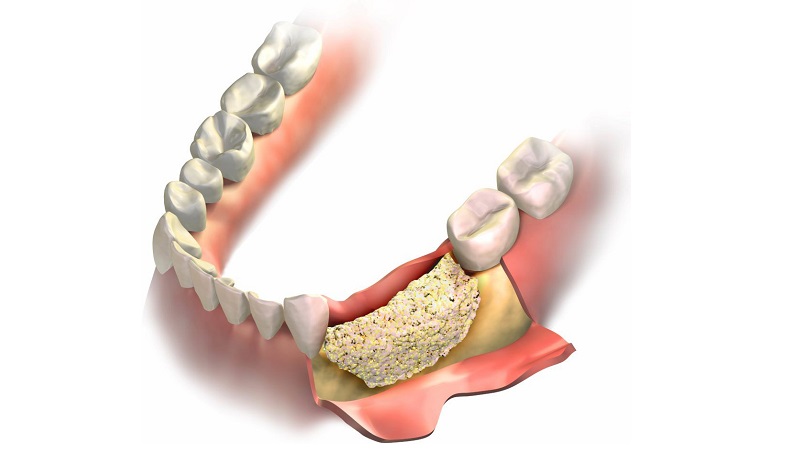

- استفاده از مواد پیوندی بعد از آن به تمیز کردن ریشهها پرداخته و ضایعات موجود در استخوان را به کمک مواد پیوندی پر خواهد کرد. در ادامه، سطح آنها با غشای خاصی پوشیده شده و مواد پیوندی روی آن قرار داده میشوند.

- بخیه محل مورد نظر پس از قرار گرفتن پیوند در جایگاه خود، جراح متخصص لثه را به قسمت درمان شده بخیه میزند. نخ بخیه معمولا ۷ الی ۱۰ روز بعد از جراحی جذب و یا کشیده میشود.

تاثیر پودر استخوان در پیوند استخوان فک

یکی از رایج ترین کاربرد پودر استخوان، استفاده از آن در ایمپلنت دندان است که به جهت افزایش تراکم و ارتقا کیفیت استخوان فک مورد استفاده قرار می گیرد. در واقع نقش اصلی این پودر برای افزایش طول استخوان، بهبود رشد آن و همچنین جایگزین شدن با قسمت های از دست رفته است. پس از پیوند استخوان، با بهبود روند گردش خون به استخوان، رشد آن تحریک میشود.